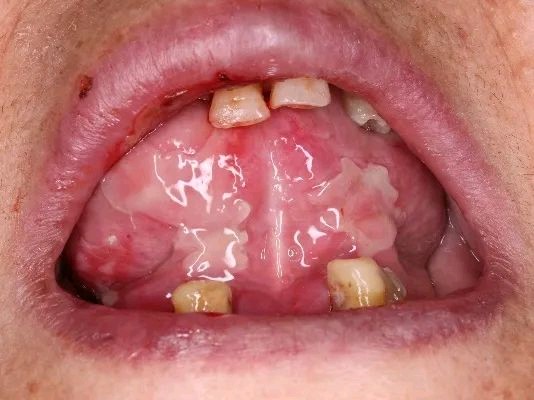

可通过口服、注射、吸入、敷贴或局部涂搽、含漱等途径进入过敏体质者机体内引起的口腔黏膜超敏反应性,可致口腔黏膜出现大面积糜烂,严重者可伴有皮损、眼部、生殖器等病损。常见的药物有解热镇痛药(如阿司匹林)、抗生素类药物(如青霉素)、中成药(如牛黄解毒片)等。因牙痛服药过敏后口腔黏膜出现大面积糜烂